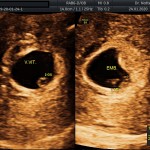

- La implantación del saco gestacional

- La edad gestacional (calculo preciso del tiempo de embarazo)

- La vitalidad embrionaria (latido cardiaco)